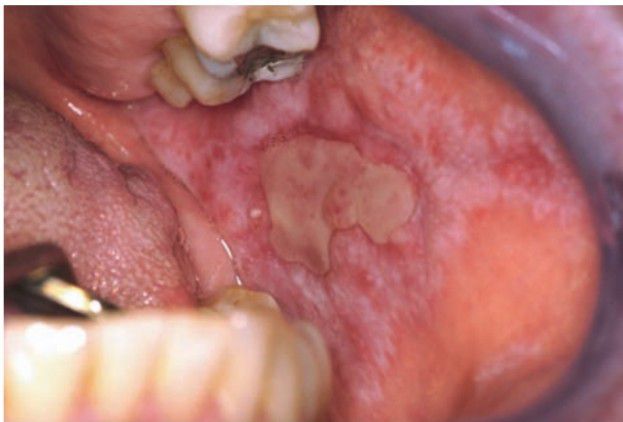

Erosive lichen planus

In the erosive form of lichen planus, the central area of the lesion is ulcerated. A fibrinous plaque or pseudomembrane covers the ulcer. The process is a rather dynamic one, with changing patterns of involvement noted from week to week.